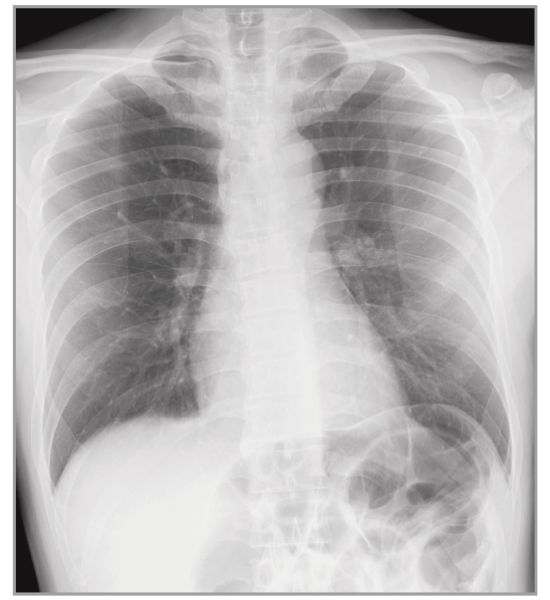

Virtual Grid

Provides a high quality image without using a grid

Virtual Grid processing corrects for the effects of scatter radiation. Without the need for a grid, Virtual Grid retains high contrast and image sharpness, while preventing the asymmetric density  resulting from misalignment of X-ray tube and detector. (Option)

Virtual Grid​

No Grid

Real Grid